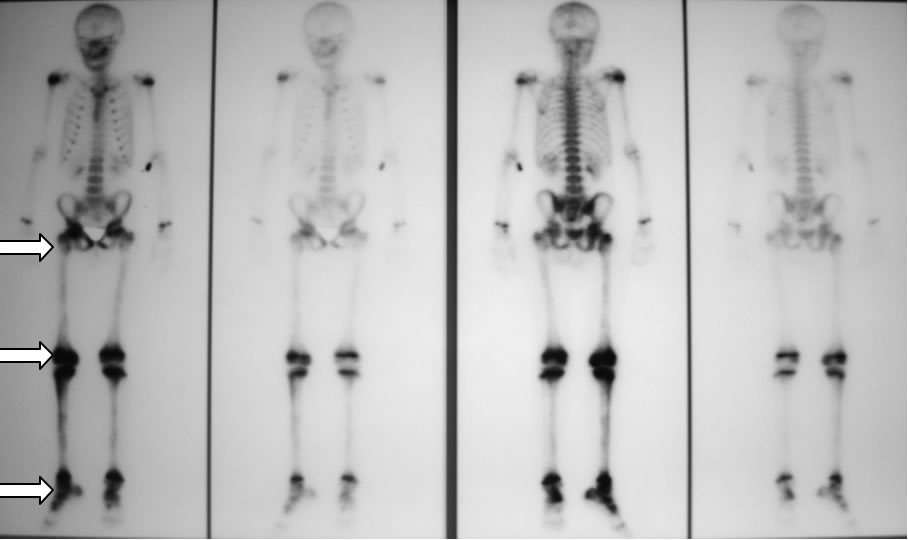

Quello che colpiva nella valutazione della diagnostica per immagini era l'aspetto, in corso di scintigrafia, di ipercaptazione di tutto il femore , non solo delle articolazioni, dato che peraltro, vista l'evidenza di artrite concomitante, non era stato particolarmente valorizzato pensando ad una generica �ipersensibilit�� della scintigrafia. (figura 1)

Figura 1: riscontro di zone multiple di captazione (ginocchio, articolazione tibio-tarsica, femore destro e coxo-femorale destra).